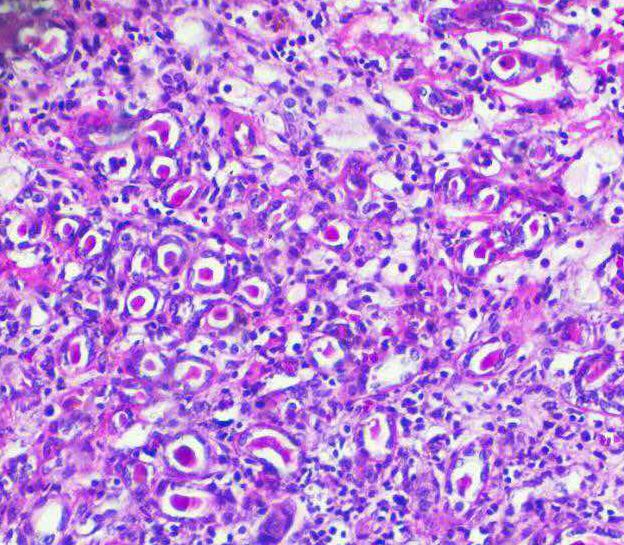

开发癌症药物的*大挑战之一是癌症类型的多样性,癌症源自多种细胞和组织,每种癌症都有自己的特征,表现和对抗癌药的敏感性...